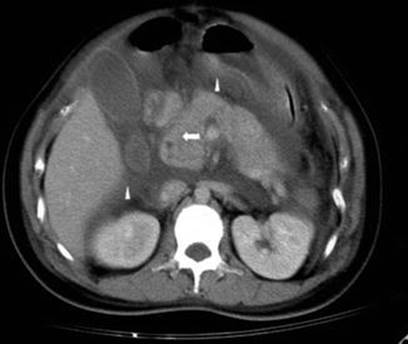

Computed tomography (CT) should be avoided, especially during the first trimester, because of radiation exposure to the fetus, but has to be performed when benefits outweighed the risk. Imaging diagnostic modalities are used not only for the diagnosis but also to provide information about the severity in AP (Figs. 3.8, 3.9, 3.10, and 3.11) [290]. In a series of 12 cases of AP in pregnant women with AFLP, Moldenhauser et al. [110] found that imaging techniques (ultrasound and computed tomography) were accurate in only 58 %. In addition, if thyroid ultrasound is equivocal, a helical CT scan is helpful in mediastinal parathyroid adenoma localization, especially during pregnancy when radioisotope techniques are contraindicated.

Fig. 3.9

Abdominal CT of a 28-year-old female in the 34th week of pregnancy with swelling of the pancreas and blurring of the mesenteric fat plane (arrow). Reactive paralytic ileus, fluid accumulation at bilateral anterior pararenal space, lesser sac, and extraperitoneal space are noted (arrowheads) [287]